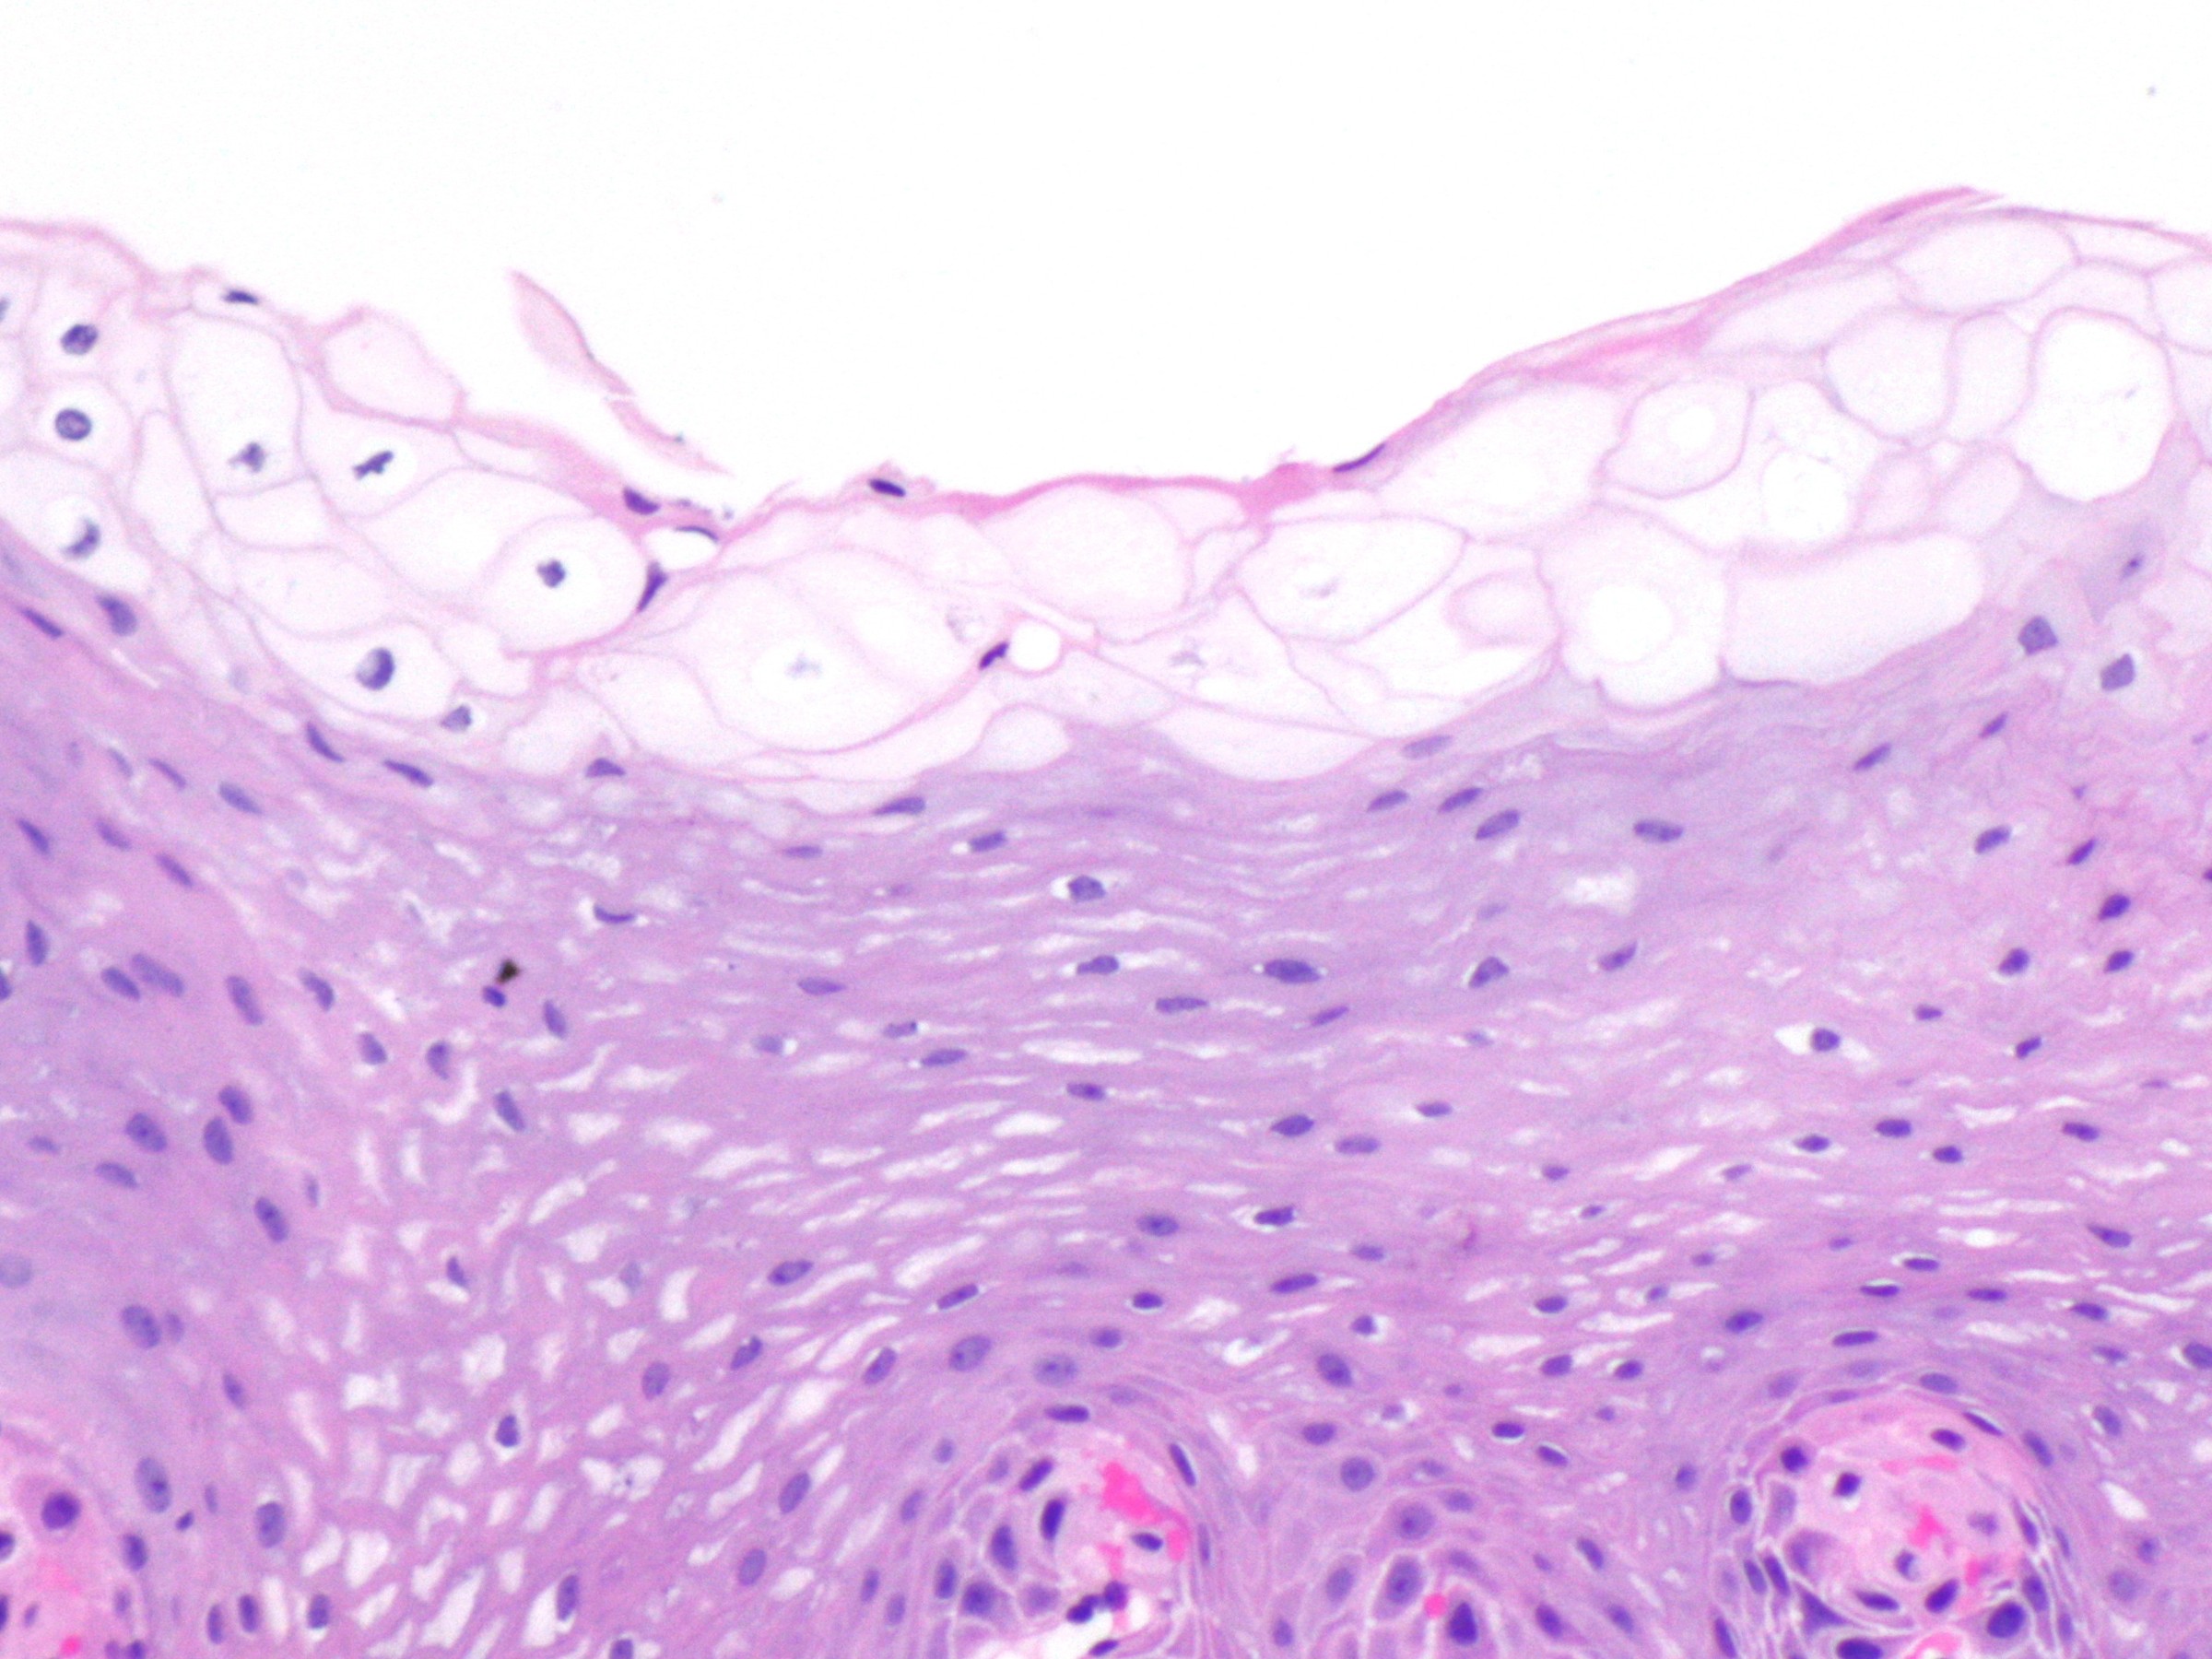

PA:

Hyperplasie van het mucosa epitheel met intracellulaire depositie van glycogeen. Geen atypie, en geen inflammatie.